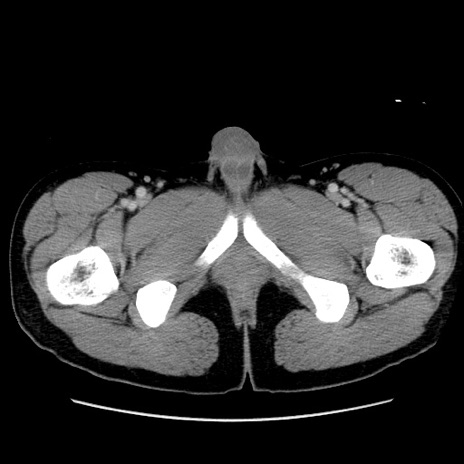

症例36(横断像)

冠状断像

【症例】20歳代 男性

【主訴】心窩部痛

【現病歴】今朝より上腹部痛あり。一旦軽快していたが再度出現したため救急要請。昨日夕に白身の魚を含む刺身を食べた。

【身体所見】BP 136/89mmHg、HR 74/min、BT 37.0℃、腹部:膨満、軟、心窩部に圧痛あり。反跳痛なし、筋性防御なし、腸雑音やや亢進あり。

【データ】WBC 17700、CRP 0.48